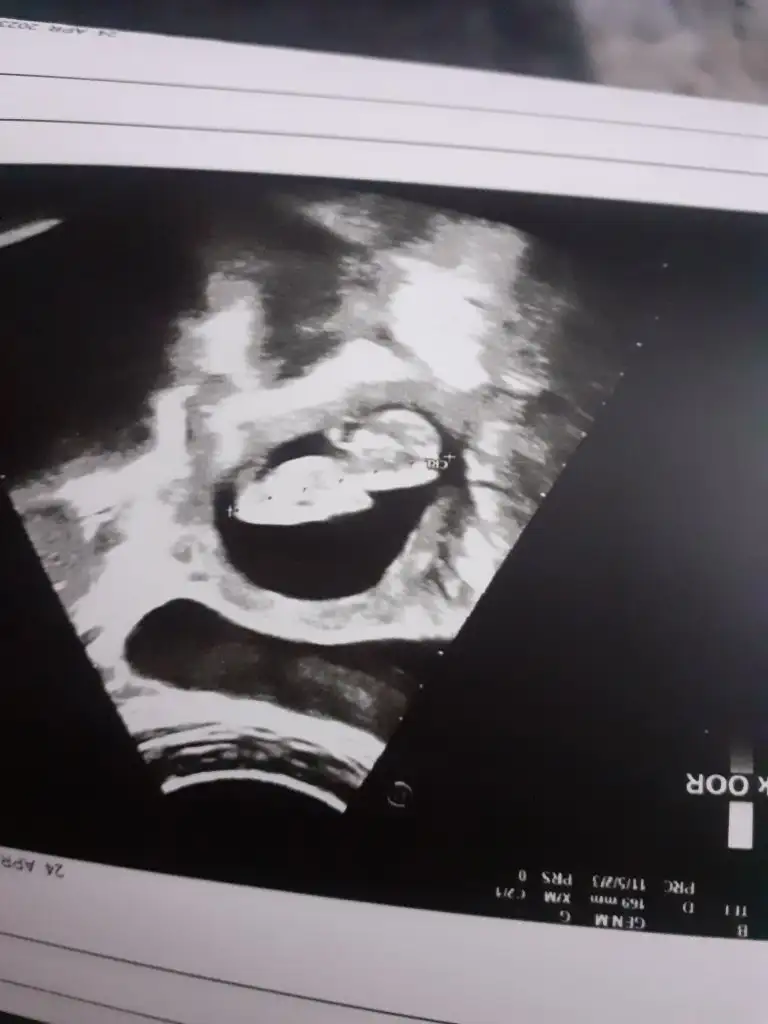

Gözünüz aydınSata göre 12+4tü ama ultrasona göre 12+2 dedi doktor. Haftası ile uyumlu dedi. Burun kemiği ense kalınlığı ve mideye baktı. Hepsi çok güzeldi. Sonra kan aldı işte. Ama pozizyonu yüzünden çok uğraştıiki kere muayaneye girdim. Cinsiyet söylemek istemedi. Daha çok küçük dedi. Zaten yüz üstüydü başta. Israr edince kız gibi derken küçük bir çıkıntı gördük. Erkeğe de benziyor dedi. Yani hem kıza hem erkeğe benzetti hahahah. Zaten başka bir seçenek de kalmıyor. Başta uyuyor gibiydi zaten. Zar sor karnımı sıka sıka hareket ettirdim. Doktor da diyor uyumuyor ama keyifçi bir de rahim şu an önde dedi. İnşallah hafta ilerledikce yukarı çıkar. Başta kanamam olmuştu. Rahim önde olduğu için olmuş olabilir dedi. Ama yukarı çıkmazsa riski cok. Bakalım ya nasip ay çok uzun yazdim neyse olsun

Eki Görüntüle 3237874